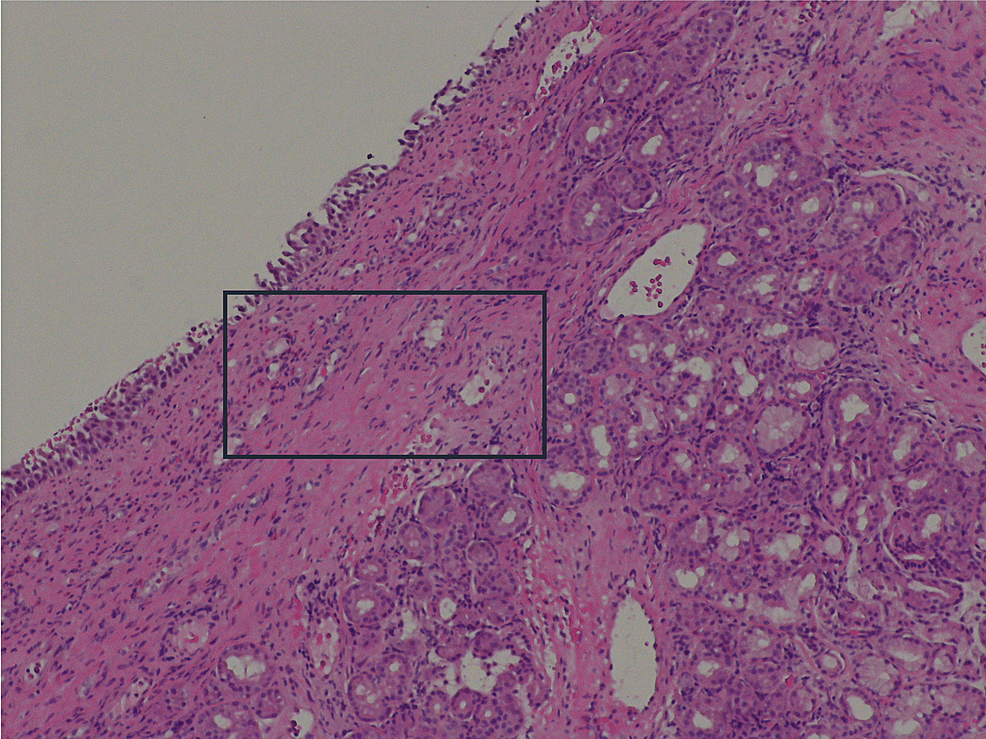

From www.cureus.com

Cureus Sinusitis and LateOnset Asthma A Red Flag of Eosinophilic Red Flags For Sinusitis This article examines the symptoms, signs, presentation, investigation, and management of nasal and sinus neoplasia, and details the ‘red. Sinusitis (also known as rhinosinusitis) is a symptomatic inflammation of the mucosal lining of the paranasal sinuses and nasal cavity. They are caused by mucosal inflammation, which inhibits mucociliary. For those with signs of acute bacterial rhinosinusitis (e.g. Acute and chronic. Red Flags For Sinusitis.

Sinusitis and LateOnset Asthma A Red Flag of Eosinophilic Red Flags For Sinusitis Acute and chronic sinusitis are common primary care presentations. They are caused by mucosal inflammation, which inhibits mucociliary. Subtypes of rhinosinusitis include acute, subacute, recurrent acute, and chronic. Rhinosinusitis is one of the most common conditions for which patients seek medical care. This article examines the symptoms, signs, presentation, investigation, and management of nasal and sinus neoplasia, and details the. Red Flags For Sinusitis.

From www.researchgate.net

(PDF) Sinusitis and LateOnset Asthma A Red Flag of Eosinophilic Red Flags For Sinusitis They are caused by mucosal inflammation, which inhibits mucociliary. Sinusitis (also known as rhinosinusitis) is a symptomatic inflammation of the mucosal lining of the paranasal sinuses and nasal cavity. For those with signs of acute bacterial rhinosinusitis (e.g. Rhinosinusitis is one of the most common conditions for which patients seek medical care. Acute and chronic sinusitis are common primary care. Red Flags For Sinusitis.

Sinusitis and LateOnset Asthma A Red Flag of Eosinophilic Red Flags For Sinusitis Subtypes of rhinosinusitis include acute, subacute, recurrent acute, and chronic. For those with signs of acute bacterial rhinosinusitis (e.g. Acute and chronic sinusitis are common primary care presentations. Acute sinusitis (also commonly known as acute rhinosinusitis) is a symptomatic inflammation of the mucosal lining of the nasal cavity and paranasal sinuses, presenting. Sinusitis (also known as rhinosinusitis) is a symptomatic. Red Flags For Sinusitis.